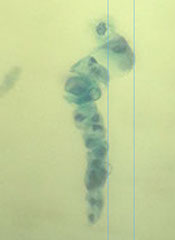

Polyomavirus

Polyomaviruses (JC and BK viruses) commonly affect urothelial cells of both healthy and immunocompromised individuals. Characteristic viral cytopathic changes are seen in 4% of urine samples. The infection usually has no clinical significance, except in immunocompromised (transplant) patients

- nickname is "decoy cells"

Cyto: Infected urothelial cells have large eccentrically placed nuclei with basophilic nuclear inclusions that completely replace the nucleus and appear glassy, opaque or cloudy.

- because of increased nuclear size and hyperchromasia, these cells are sometimes confused with malignant cells – hence their pseudonym “decoy cells”. However unlike most malignant cells , decoy cells have perfectly smooth and round nuclei.